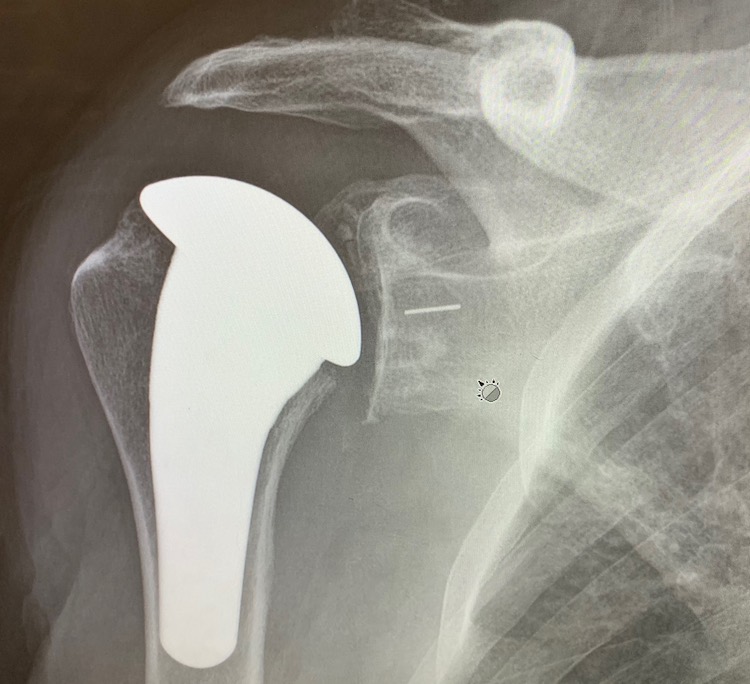

Here is the proof of my new shoulder. The new titanium ball is nicely fitted into my humerus, the long bone in the upper arm between the elbow joint and the shoulder. It took a highly skilled surgeon with hammer, saw, and drill to get it there, which explains the pain and long recovery time to get back to normal. You can’t see the socket of the prosthetic ball and socket pair. The socket is plastic and does not show up in the x-ray. The short white line to the right is the screw in the center of socket fastening it to the glenoid. One thing I am sure about: the new ball and socket will be there for the duration. If you want to see the toolkit and parts used to create the new shoulder joint, look here.